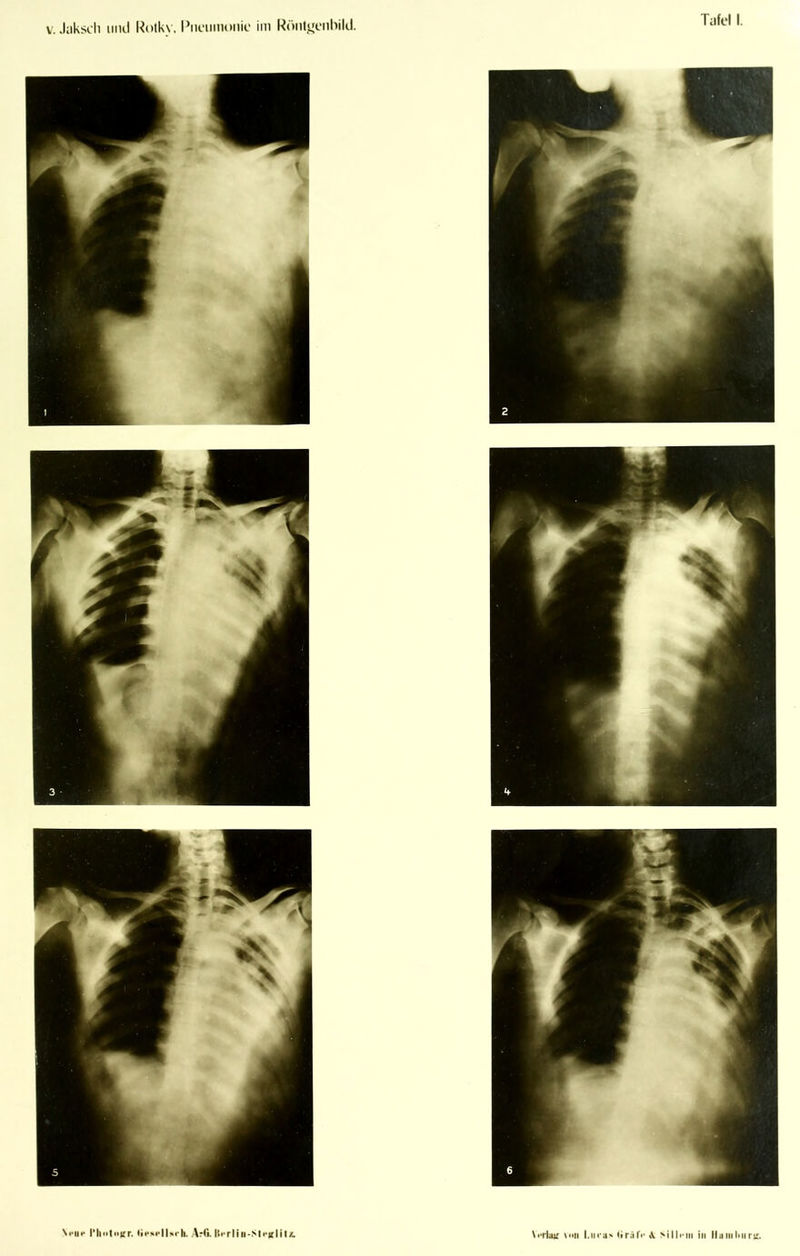

Die Pneumonie im Röntgenbilde ... : mit 59 Röntgenbildern auf 10 Tafeln und 10 Skizzenblättern / von R.v. Jaksch und H. Rotky.

Credit: Die Pneumonie im Röntgenbilde ... : mit 59 Röntgenbildern auf 10 Tafeln und 10 Skizzenblättern / von R.v. Jaksch und H. Rotky. Source: Wellcome Collection.